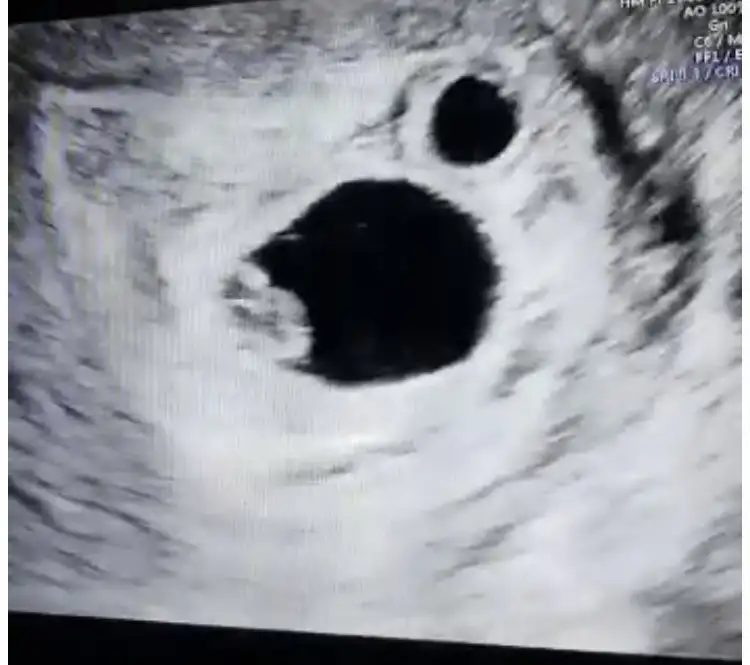

bence kız sağ tarfta plasentaEki Görüntüle 2780164 Eki Görüntüle 2780165 merhabalar bir tahmin de ben isteyeyim 9+3 ve 7+² ye ait fotoğraflar her ikisi de karından usg

Erkek sankiEki Görüntüle 2780164 Eki Görüntüle 2780165 merhabalar bir tahmin de ben isteyeyim 9+3 ve 7+² ye ait fotoğraflar her ikisi de karından usg

Teşekkürler bakalim ben de bilmiyorumbence kız sağ tarfta plasenta